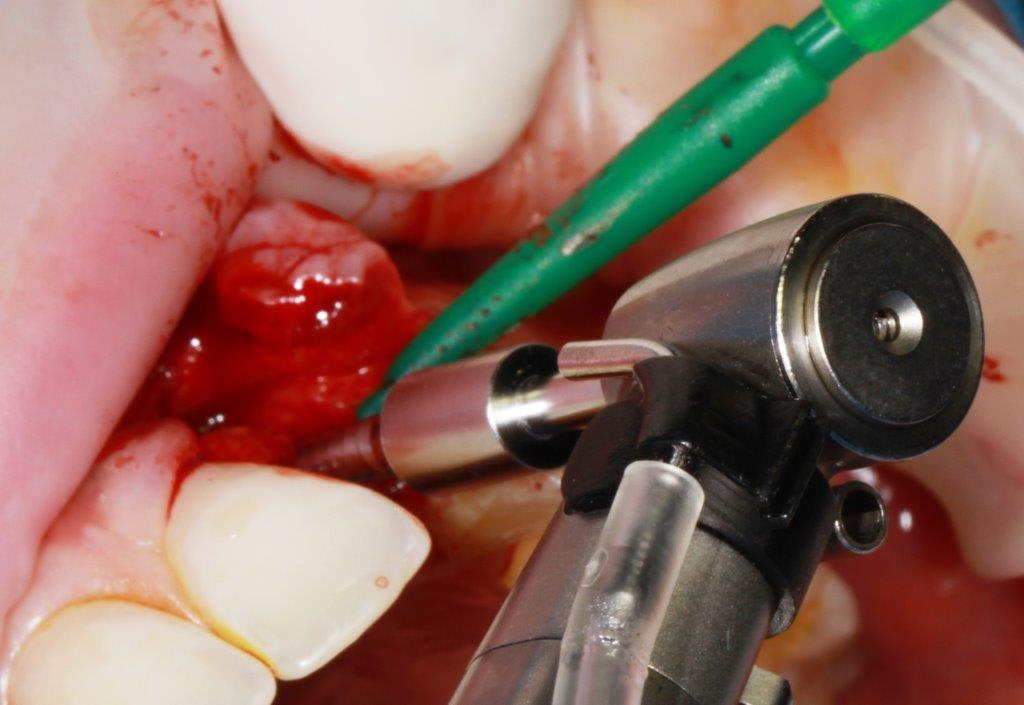

pour ceux que ça intéressent, une petite utilisation d'expansion de la paroi palatine, sur une avulsion d’incisive(racine fendue). toutes mes excuses pour la mauvaise qualité des photos.